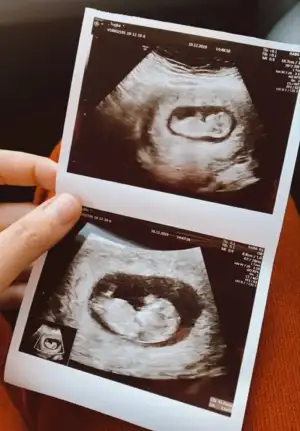

Kaç haftalık sanki kız gibi ama 11+ yada 12+ olmalı usg buyuk görünüyor gibi 13+ sonrası organ tamamlanmış oluyorMerhabalar bu bebise de bakar misiiz kiz mi erkek mi

Hadi ya bu da mı erkek acaba bi erkek oğlu daha var da açıklanınca haber verirm artık teşekkürler canım10+2 hafta nub iki tarafa benzer 11+ yada 12+ olmalı usg ama şimdilik erkek gibi gibi ekliyorum![]()

Şimdilik erkek gibi 11 yada 12 hafta usg paylaşın daha net olur nubuHadi ya bu da mı erkek acaba bi erkek oğlu daha var da açıklanınca haber verirm artık teşekkürler canım ☺

Doktorda kiza benzetti ama emin degilim haftaya daha net soylerim dedi yine atacagim sana canımKız gibi kafa şekli ama tutmaya bilir![]()